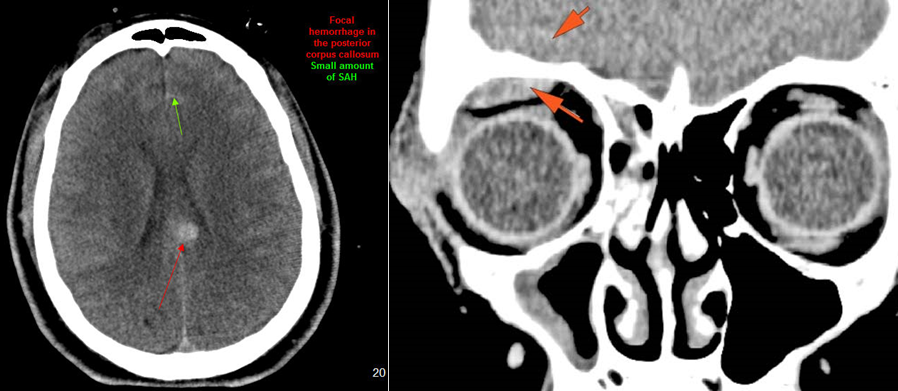

There is subperiosteal, epidural or subdural hematoma and/or pneumocephalus along the boney walls of the anterior, middle or posterior cranial fossa or elsewhere. [Yes/No]

There is subarachnoid blood. [Yes/No]

There is parenchymal brain injury, brain herniation and/or hydrocephalus. [Yes/No]